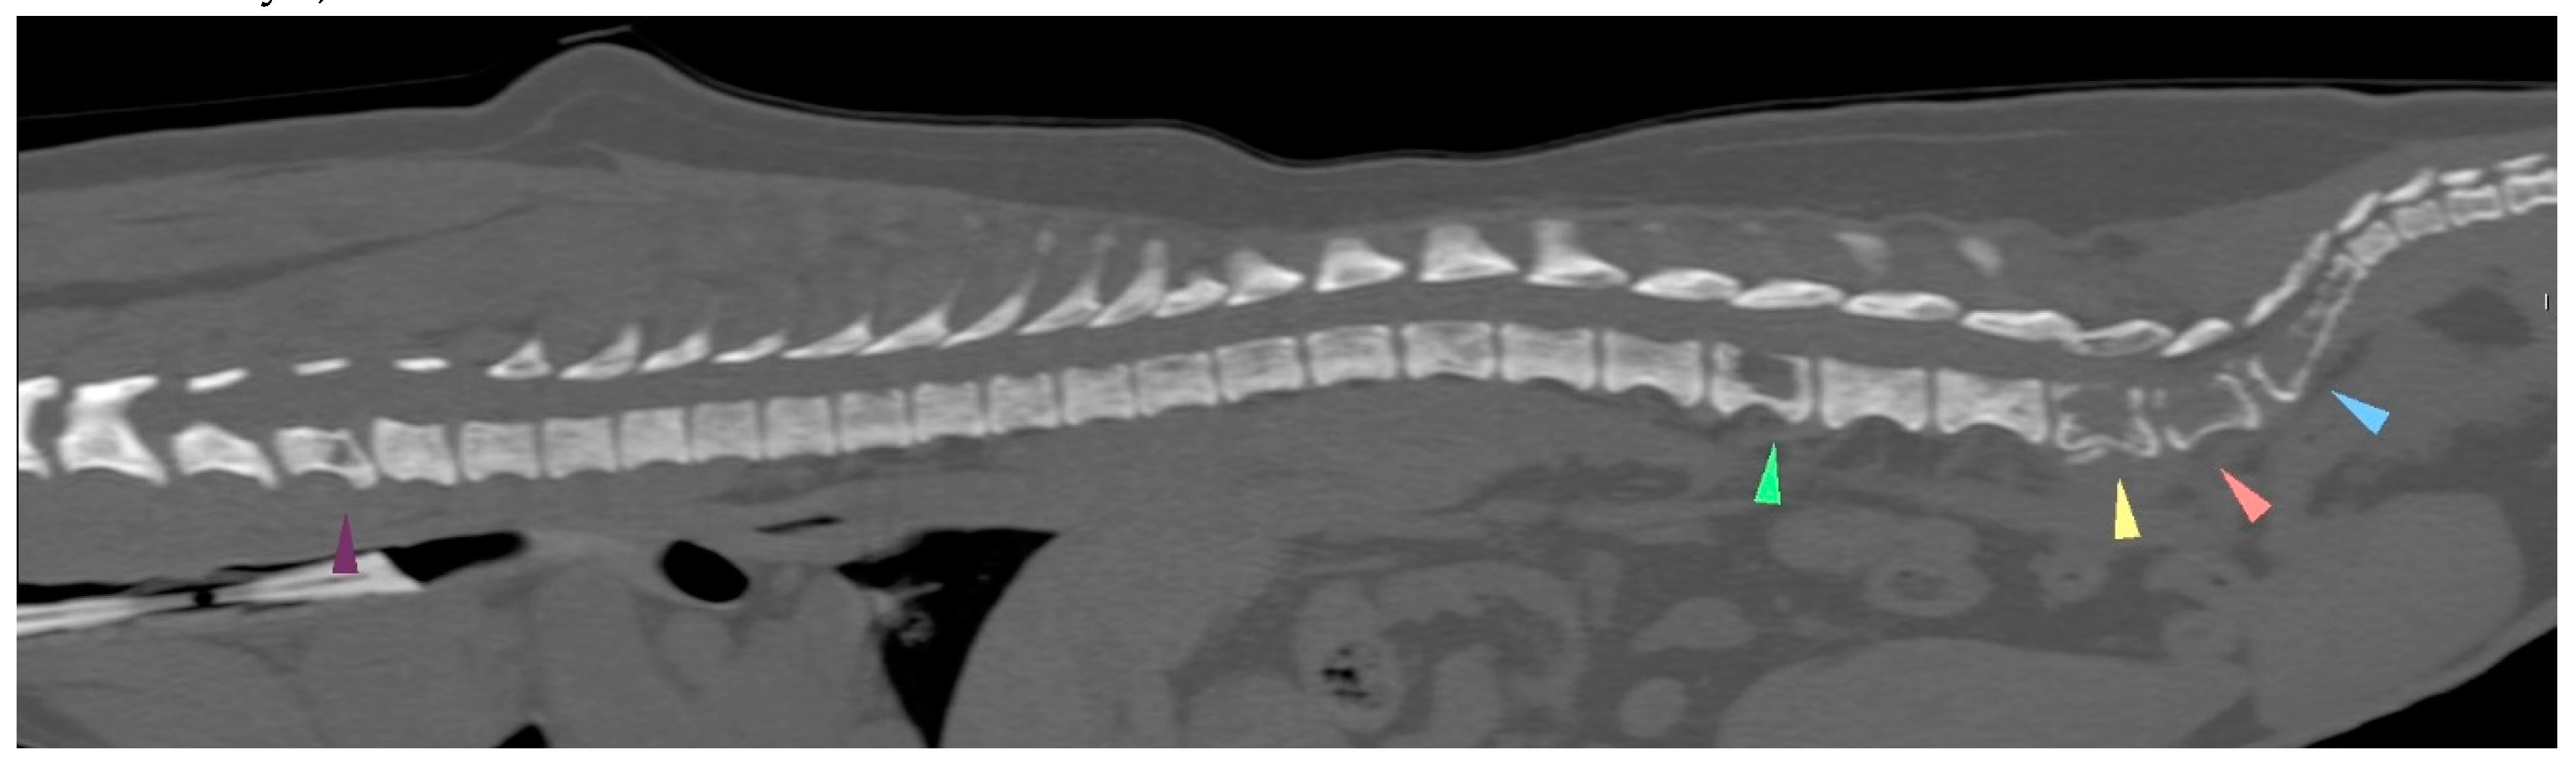

| 21/09/01 | flaccid tail, evolving into posterior paresis within 24 hours spinal metastases (CT examination) and death on 21/09/22 |